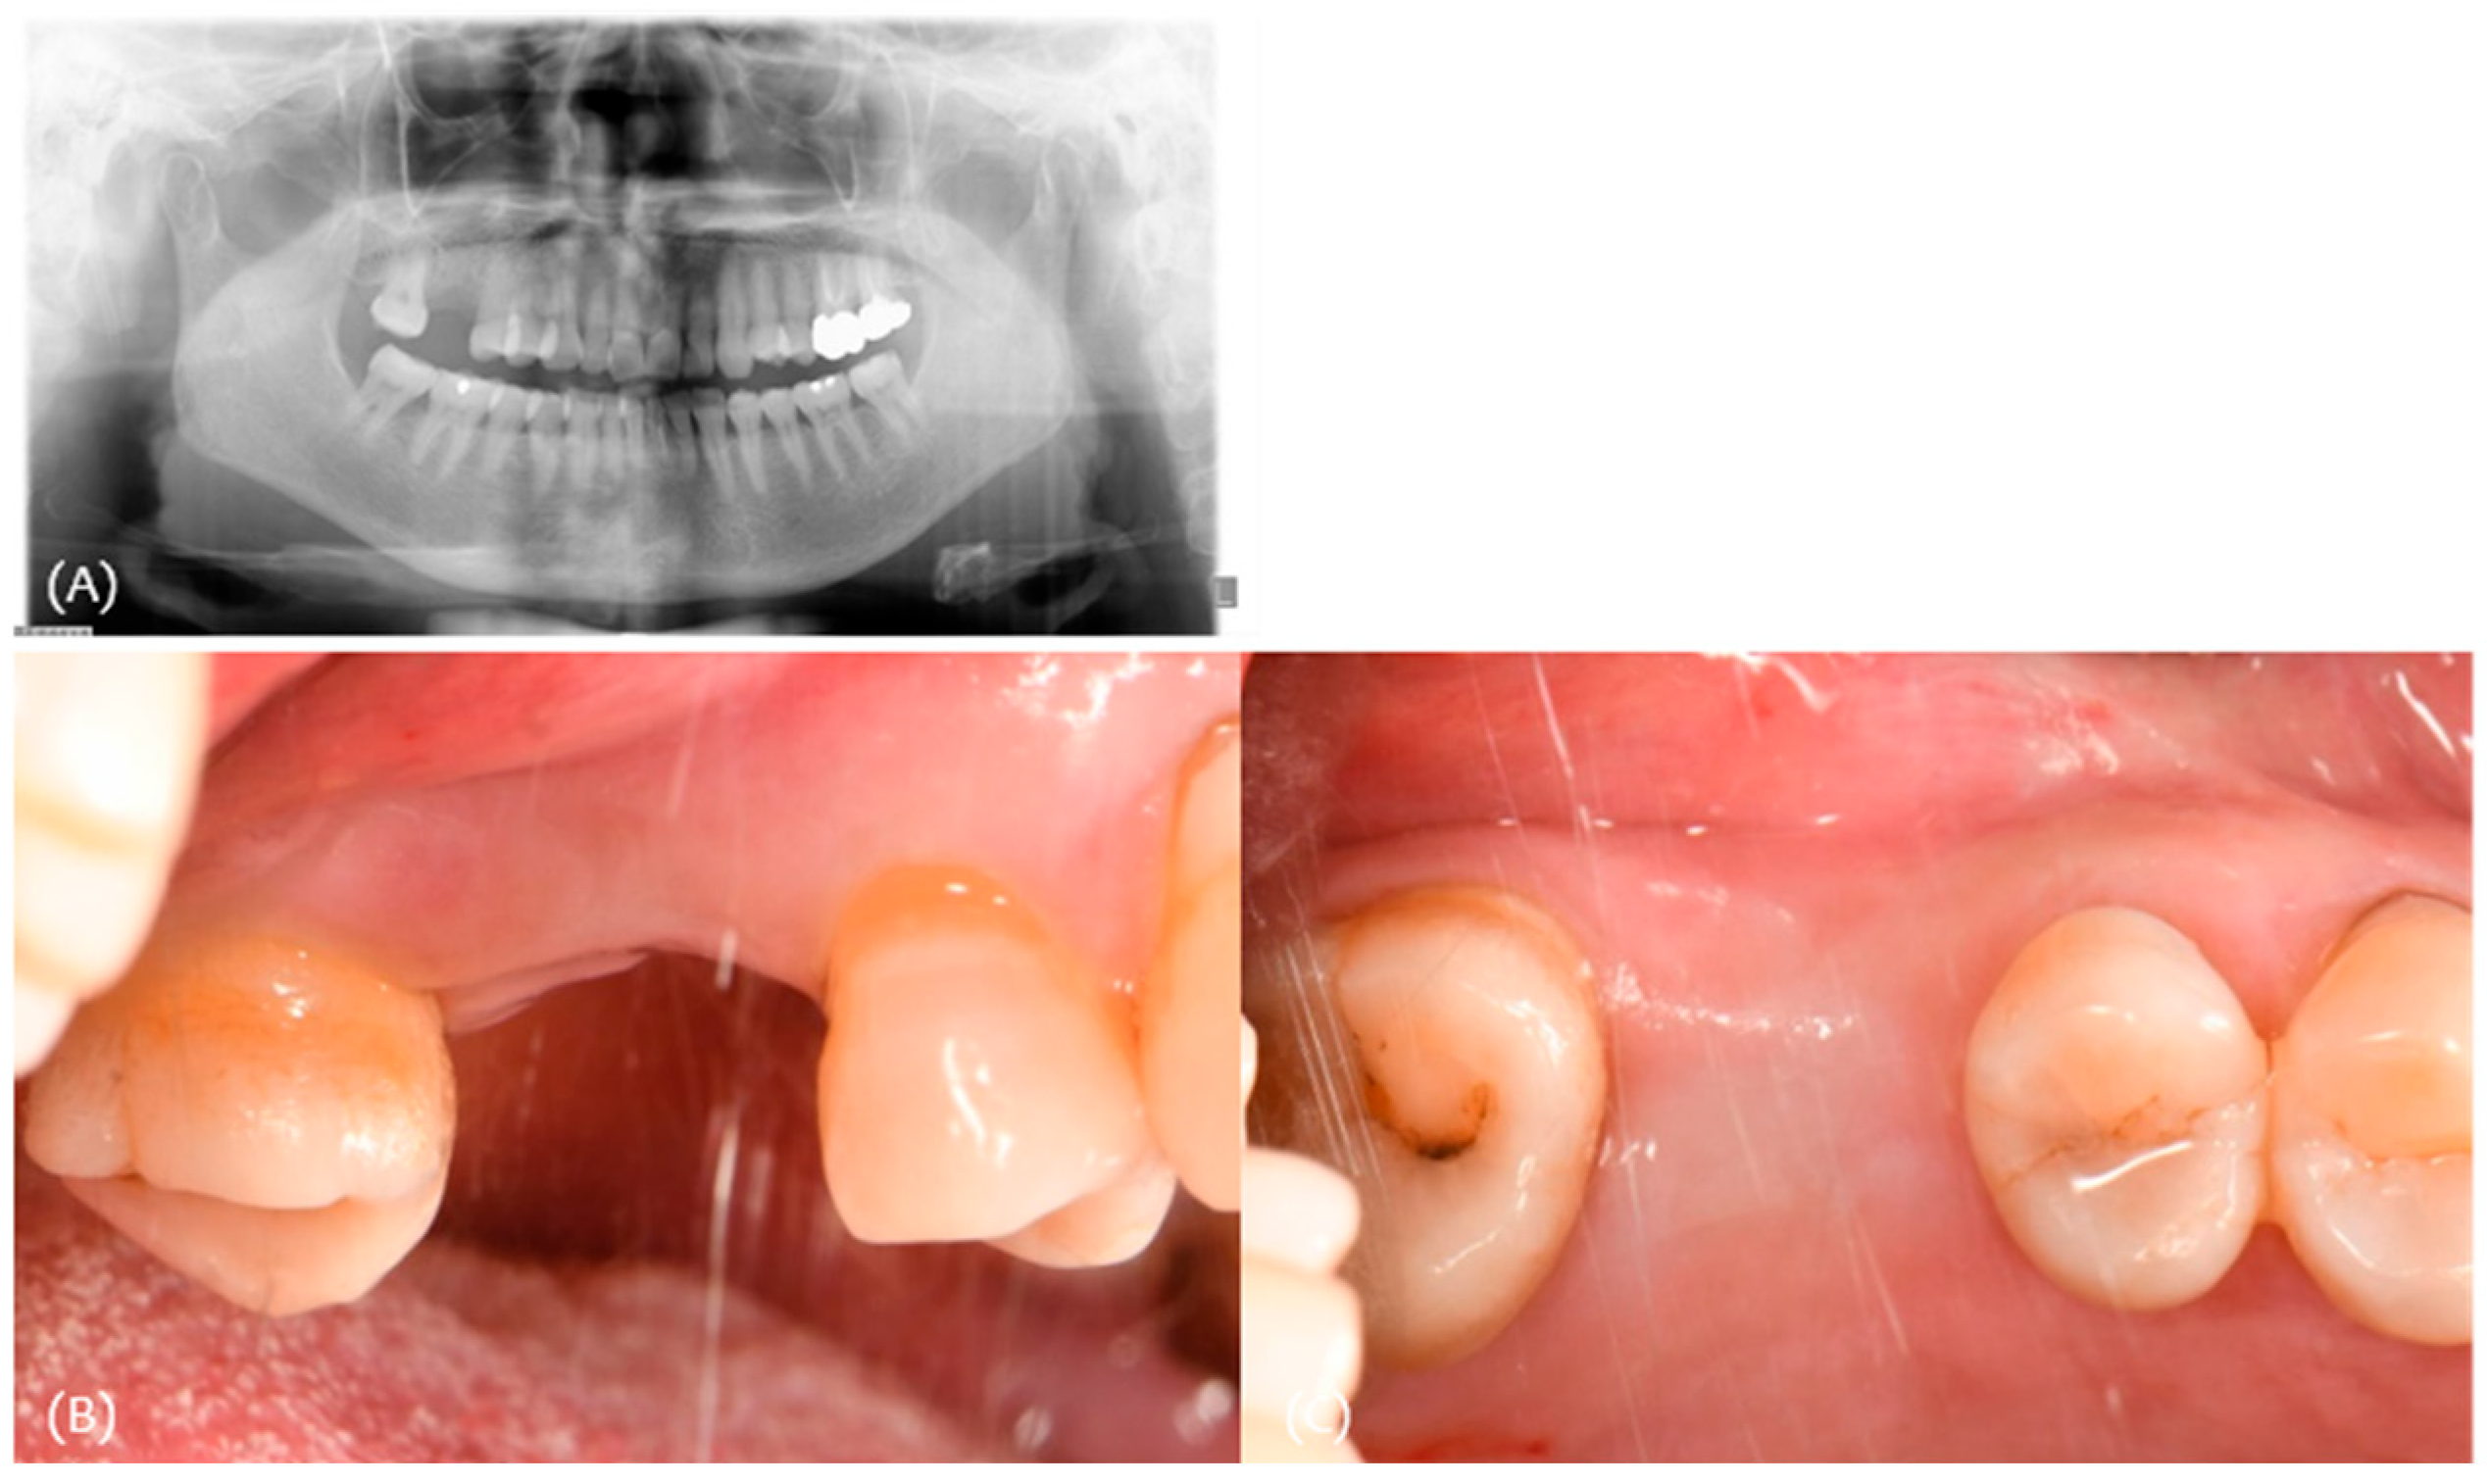

3.1. Case 1

| #17 | #16 | #15 | |

|---|---|---|---|

| Classification (Seibert) | Class I | ||

| Amount of maximum concavity (mm) | 3.5 | ||

| Buccal pocket depth (mm) | 433 | 332 | |

| Palatal pocket depth (mm) | 443 | 333 | |

| Bleeding on probing | - | - | |

| gingival recession (mm) | 000 | 010 | |

| Keratinized tissue Width (mm) | 4 | 5 | 5 |

| Site | Pre-Op Concavity (mm) | Increased Buccal Soft Tissue Volume 2 Weeks After Op (mm) | Increased Buccal Soft Tissue Volume 4 Months After Op (mm) |

| Distal | 1.3 | Δ 2.61 | Δ 0.959 |

| Disto-middle | 2.9 | Δ 3.2 | Δ 1.43 |

| Middle | 3.5 | Δ 3.13 | Δ 1.7 |

| Mesio-middle | 3.2 | Δ 3.01 | Δ 1.42 |

| Msesial | 2 | Δ 1.36 | Δ 1.06 |

| Average | 2.58 | Δ 2.662 | Δ 1.3138 |